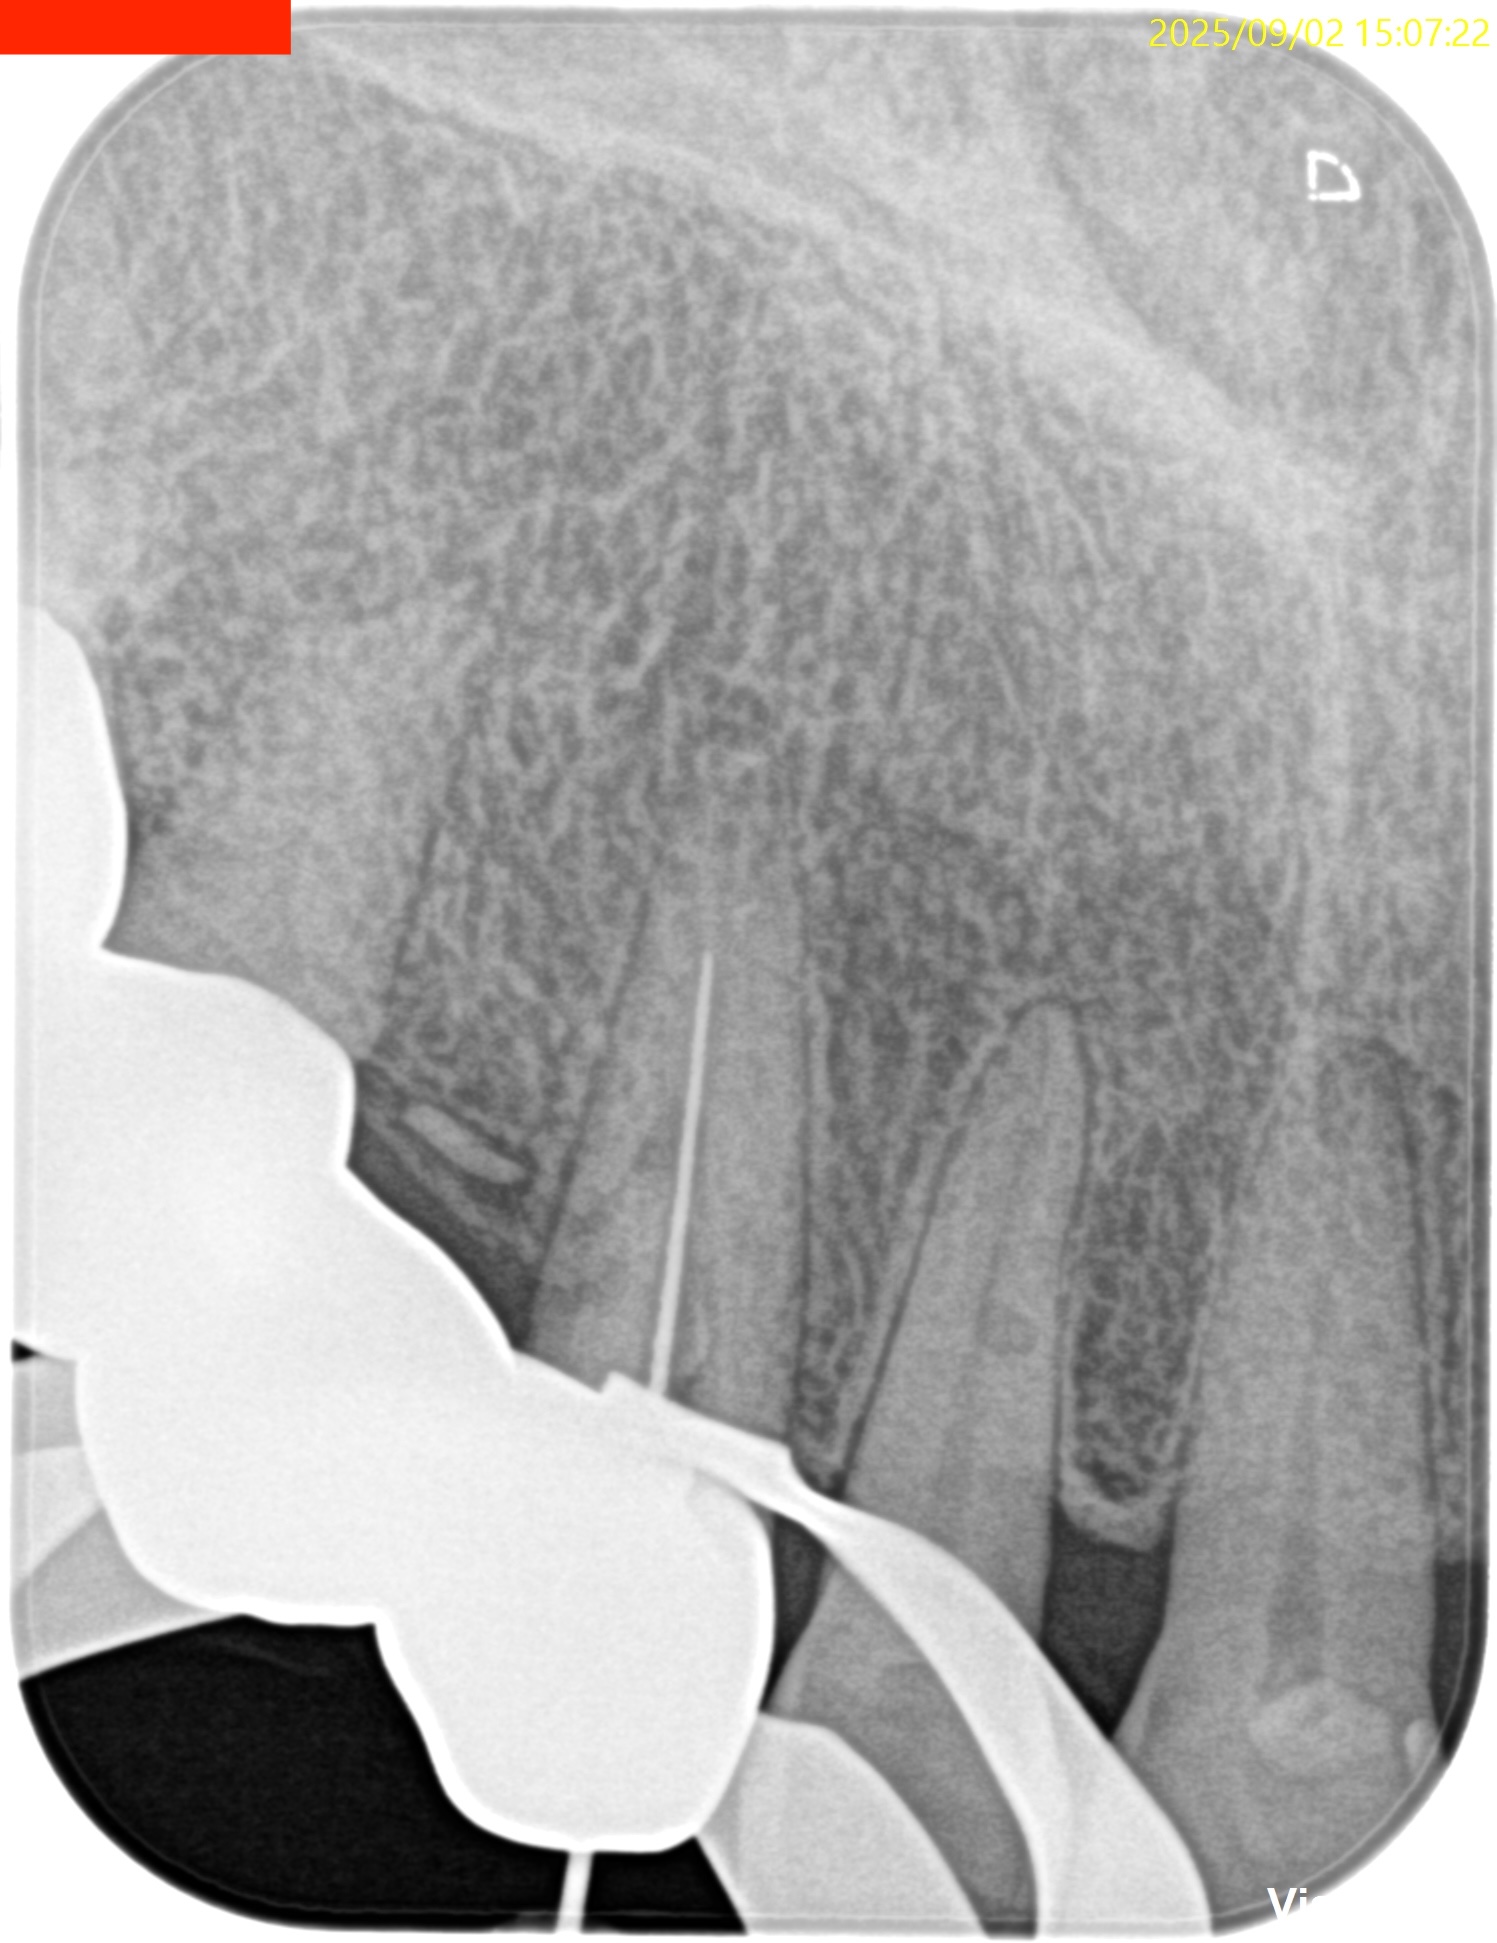

#6 Invasive cervical root resorption repair, RCT/Apicoectomy(2025.9.2)

Flapを開けてまず外部吸収部位を特定した。

縫合後に、根管治療を試みるが…

とんでもない方向に穿孔していた。

ということでこの時点で非外科的な歯内療法の選択肢が消滅した。